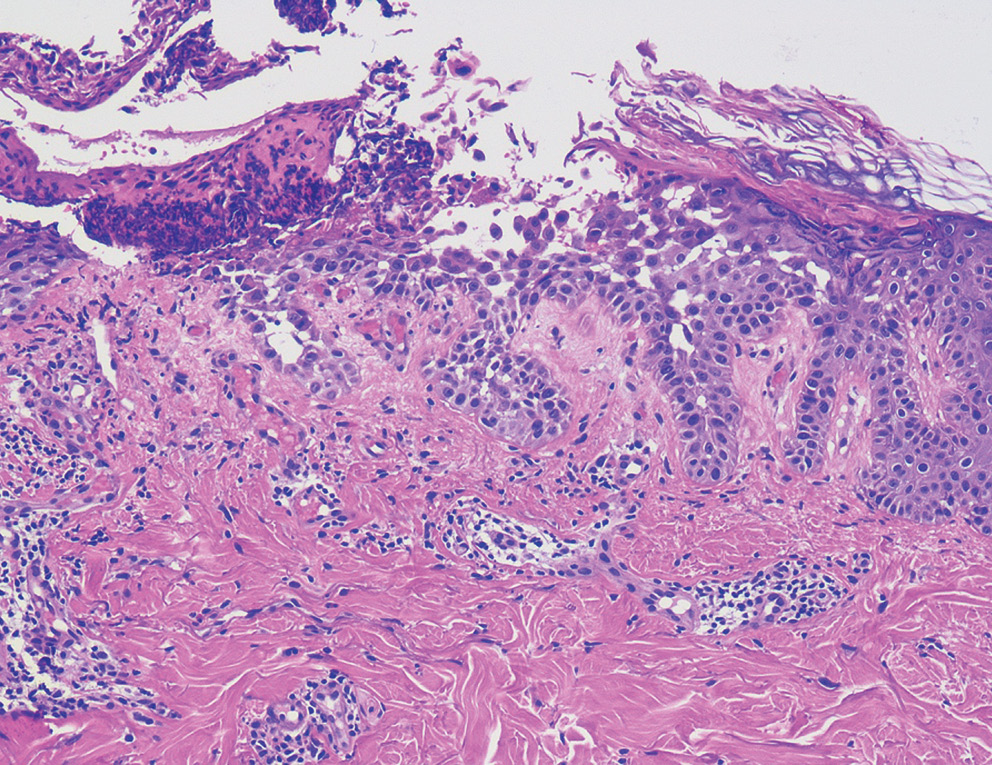

При гистологическом исследовании болезни Гровера наиболее часто встречающимся морфологическим вариантом является Дарье-подобный, который характеризуется наличием акантолиза с явлениями дискератоза в виде образования так называемых «круг- лых телец» и «зерен» в эпидермисе (рис. 4). Другие гистологические варианты заболевания включают спонгиотический, пемфигус-подобный (обычно гистологическая картина при данном варианте имеет сходства с вульгарной/листовидной пузырчаткой) и Хейли–Хейли-подобный [2] (рис. 5, 6). Спонгиотический вариант характеризуется наличием спонгиотической внутриэпидермальной полости, пемфигус-подобный — акантолизом на разных уровнях эпидермиса, Хейли–Хейли-подобный — гиперплазией эпидермиса с явлениями акантолиза в виде «рушащейся кирпичной стены». Разные гистологические варианты заболевания могут сочетаться у одного пациента (рис. 7).

Рис. 4. Дарье-подобный гистологический вариант болезни Гровера: акантолитический дискератоз с дискератотичными клетками в верхних отделах эпидермиса

Fig. 4. Darye-like histological variant of Grover’s disease: acantholytic dyskeratosis with dyskeratotic cells in the upper epidermis

Рис. 6. Хейли–Хейли-подобный вариант болезни Гровера: в эпидермисе акантоз, явления акантолиза по типу «рушащейся кирпичной стены»

Fig. 6. Hayley–Hayley is a similar variant of Grover’s disease: acanthosis in the epidermis, acantholysis phenomena of the «crumbling brick wall» type